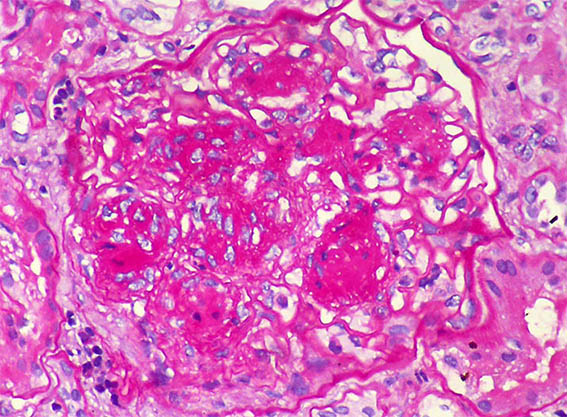

Figura 2. PAS, X400.